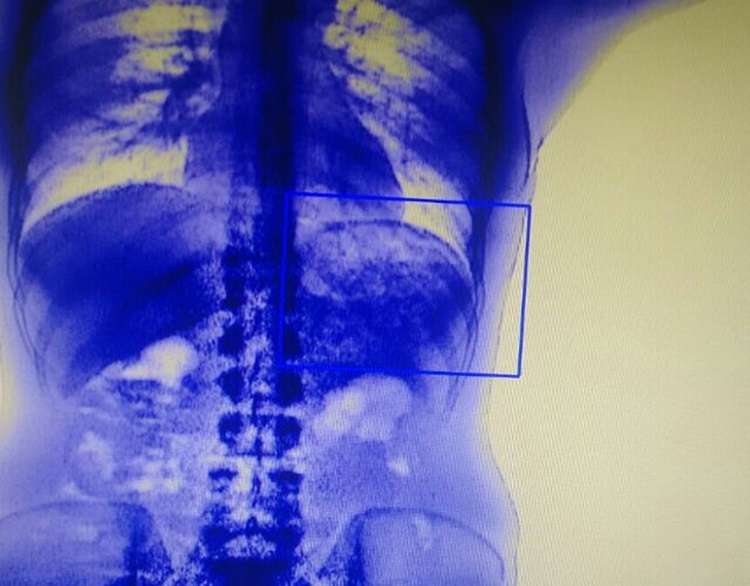

No regresso do saidão do Dia dos Pais, nove presos do Centro de Internamento e Reeducação (CIR), no Complexo Penitenciário da Papuda, foram flagrados com 190 porções de maconha, crack, cocaína e roupinol no estômago, embalados em preservativos e plásticos.

Eles engoliram as drogas e pretendiam vendê-las dentro da cadeia. O grupo foi descoberto durante uma operação da Subsecretaria do Sistema Penitenciário (Sesipe), que contou com o auxílio de um scanner corporal. Dos 105 detentos vistoriados, 12 eram suspeitos do carregamento ilegal e foram encaminhados para o Instituto Médico Legal (IML).

Depois de comprovado o envolvimento dos nove, eles foram transportados ao Hospital Regional da Asa Norte (HRAn), onde tiveram os entorpecentes expelidos, antes de chegarem na 30; Delegacia de Polícia (São Sebastião), onde foram autuados por tráfico de drogas.